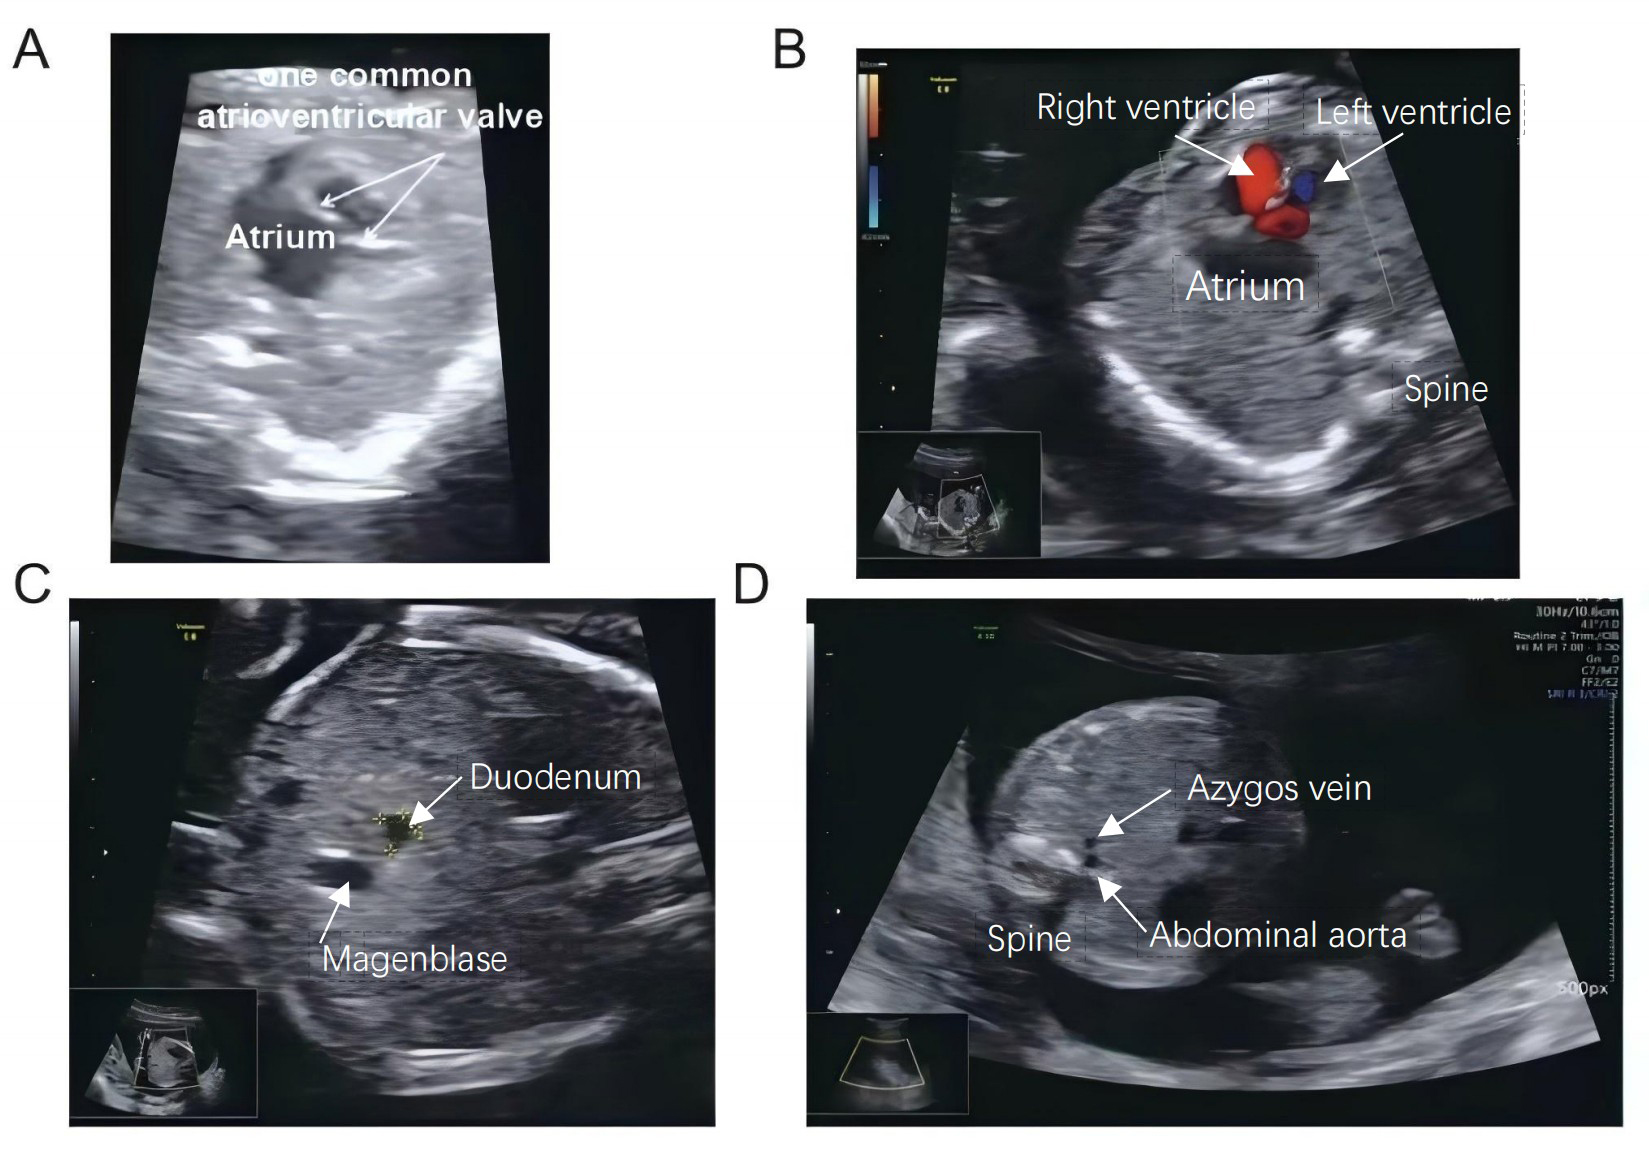

Heterotaxy syndrome is characterized by abnormal organ arrangement across the left-right (L-R) axis, often leading to complex congenital heart defects (CHDs). Genetic analysis via whole-exome sequencing revealed two novel compound heterozygous mutations in the polycystic kidney disease 1 like 1 (PKD1L1) gene (NM_138295.3: c.6659T>A and c.8104dup). These genetic alterations are implicated in the abnormal development of the L-R axis, contributing to the severe cardiac malformations observed.

This case report describes a Chinese fetus diagnosed with heterotaxy and severe cardiac anomalies identified through prenatal ultrasound.